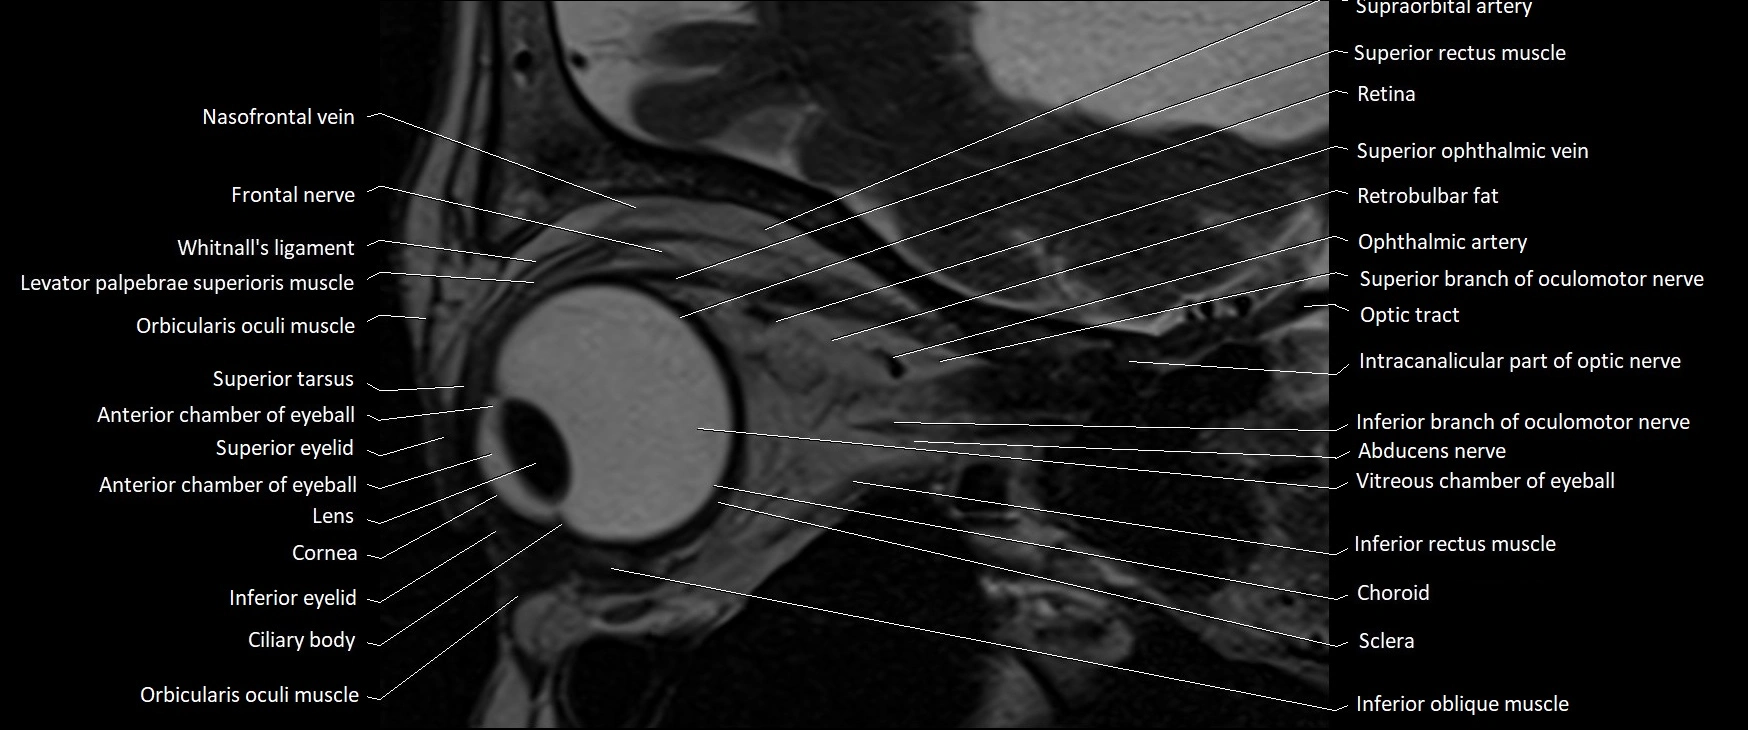

MRI images